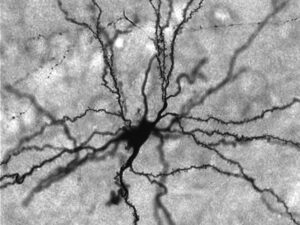

Una tecnica per cancellare selettivamente ricordi traumatici

I ricercatori hanno trovato il modo per eliminare in modo permanente i ricordi dolorosi. Questo potrebbe portare a sviluppare nuovi...